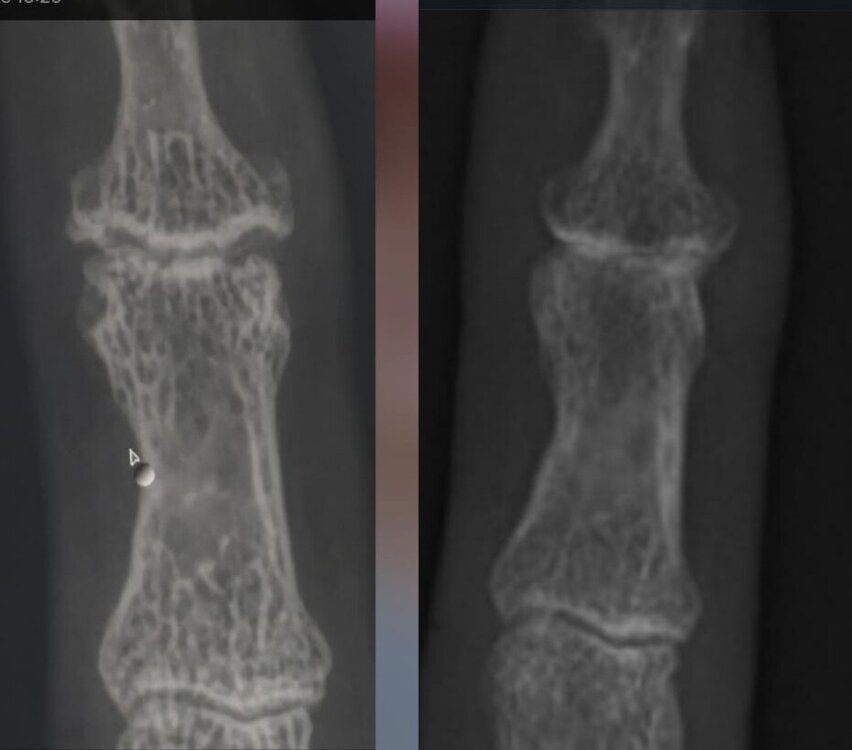

Ist das eine Schuppenflechte oder nicht?